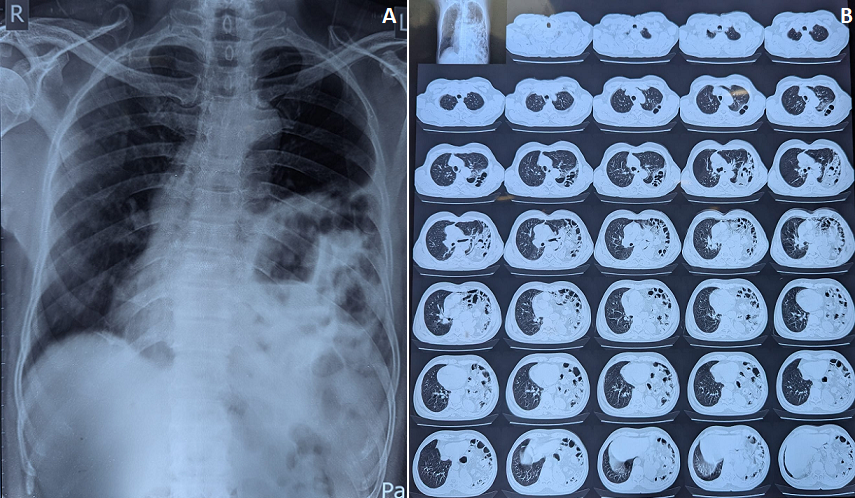

A 60-year-old man presented to the emergency department with an 8-day history of progressive breathlessness. He reported a head-on motor vehicle collision 10 years earlier but remained asymptomatic and was never evaluated at that time. Clinical examination revealed markedly reduced air entry over the left hemithorax, with audible bowel sounds in the same region. Chest radiograph (image A) and high-resolution computed tomography (HRCT) thorax (image B) demonstrated a large ~5.8 cm posterolateral defect in the left hemidiaphragm, consistent with a Bochdalek hernia, with herniation of the stomach and small bowel loops into the left thoracic cavity. Associated rightward mediastinal shift and mild compressive atelectasis of the left lung were noted. The patient underwent prompt surgical repair with complete relief of symptoms. This case highlights the need for thorough evaluation following thoracoabdominal trauma-even in asymptomatic individuals-and reinforces that delayed presentation of traumatic Bochdalek hernia, though rare in adults, is a surgical emergency due to the risk of incarceration and strangulation.